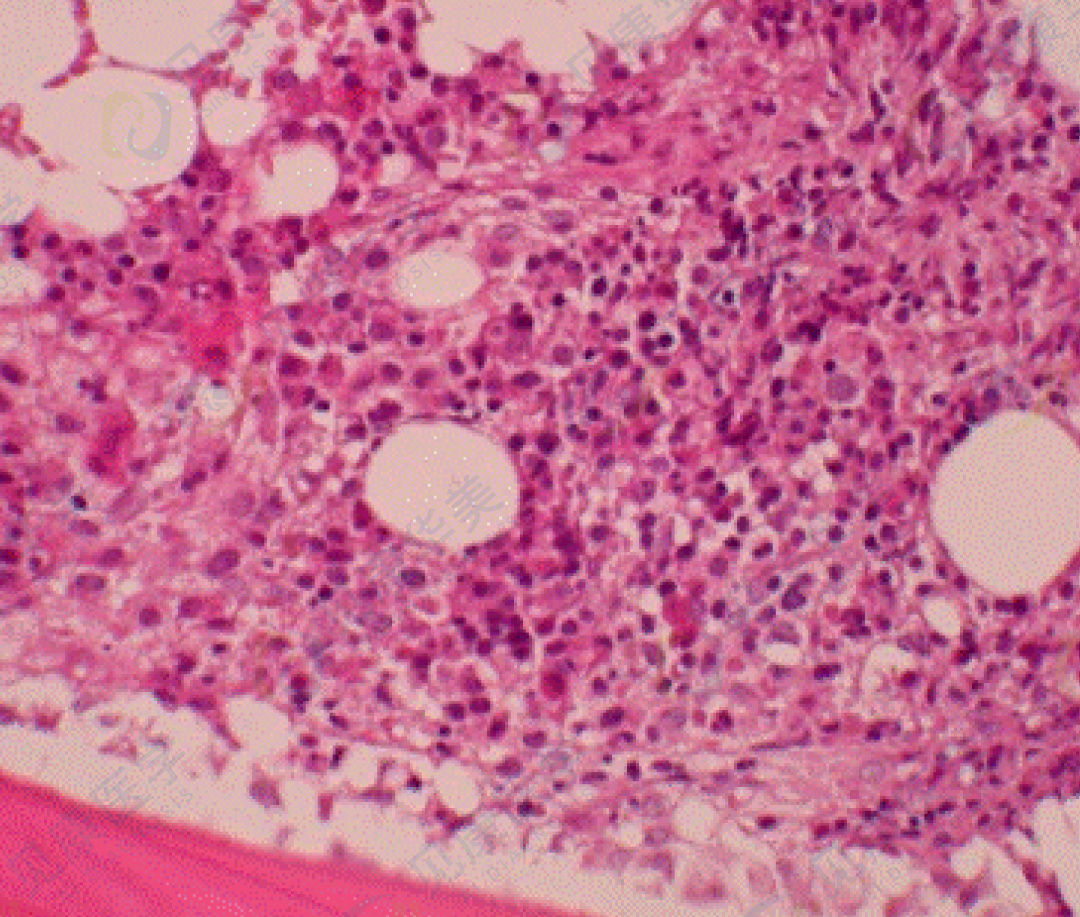

T-LGLL骨髓受累相对较轻,单靠形态学识别较为困难。骨髓活检中的LGL与正常淋巴细胞相似,为小淋巴细胞。由于标本制备过程中组织收缩(制备后骨髓活检组织收缩约20%),切片中淋巴细胞胞浆极少或见不到胞浆,无法观察嗜天青颗粒。T-LGLL的骨髓活检典型表现为淋巴细胞的窦内分布,串珠或列兵样排列,伴有反应性淋巴细胞灶(CD4+细胞为主)。

骨髓活检切片,T-LGLL呈间质型分布,可见窦内浸润(免疫组化CD3染色)。